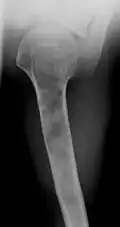

X-ray showing enchondromas localized in the humerus of a 37-year-old patient affected with Ollier disease -

Enchondromas localized in the upper part of the humerus of the same patient